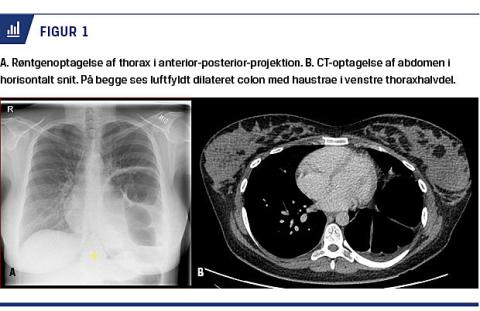

Der blev foretaget røntgenoptagelse af thorax og CT af abdomen (Figur 1), hvilket gav mistanke om et stort Bochdalekhernie, hvor venstre thoraxhalvdel indeholdt colon descendens og delvist colon transversum samt en dilateret colon ascendens.

Bochdalekhernier visualiseres bedst med CT, hvor man dels kan se defekten af diafragma, dels dilaterede tarmslynger og bløddelsfortætning superiort for diafragma i det posterolaterale område.